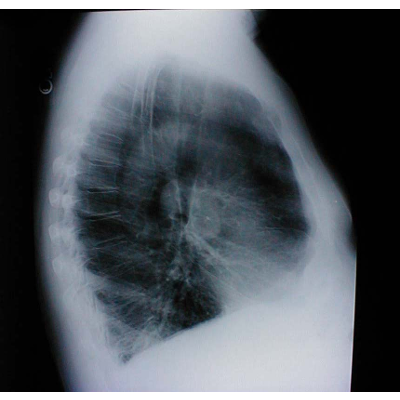

Discusses the basics of lung auscultation and examinations. Includes abnornals, anatomy and physiology graphics, etc.